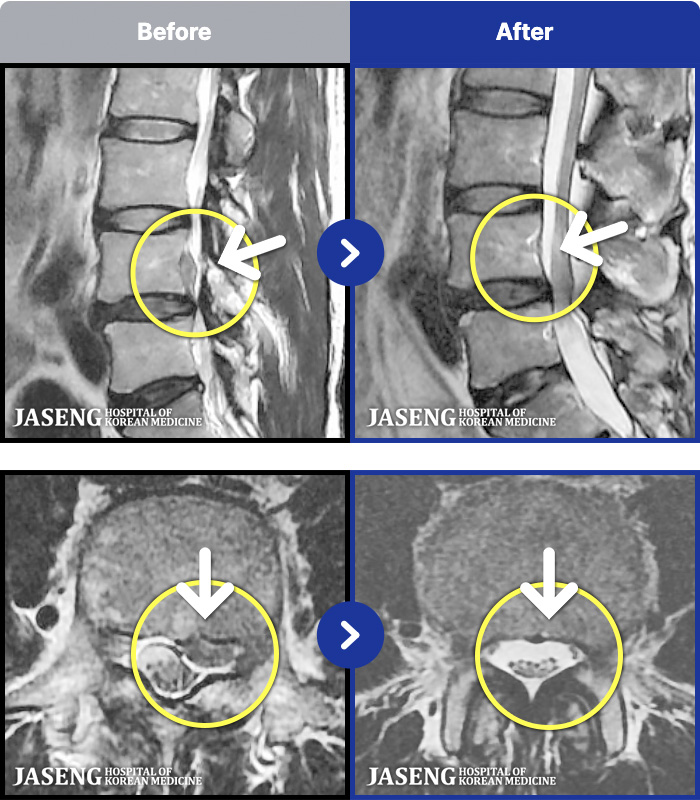

MRI ġ

1,301 MRI ũ ʸ Ȯϼ.